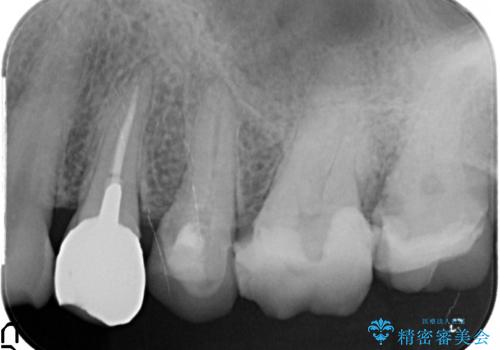

放置してしまった深い虫歯の治療

- 虫歯治療を中断し放置、痛みが出てきたため当院を初診来院されました。

虫歯の深化により根管治療、歯周外科手術を行い歯肉の状態を改善し精密なセラミッククラウンを製作する治療を計画します。

セラミック治療の長期的な予後を見込むために、根管治療、歯周外科を行いクラウン装着前の環境を整えておくことが肝要です。